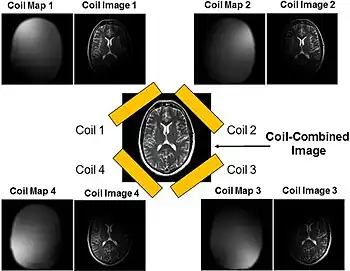

Parallel imaging

Parallel imaging involves the addition of multiple coils surrounding the target with each coil acquiring a fraction of the total image. Because modern GPUs have parallel processing capabilities, they can reconstruct each portion of the image simultaneously. Therefore, the more coils used, the faster the acquisition of the MR images.[15]

SENSitivity Encoding (SENSE)

Certain image reconstruction algorithms used alongside parallel imaging address the potential issues that can arise from undersampling the k-space. SENSitivity Encoding (SENSE) is a method that reconstructs the partial k-space data from each coil and combines the partial images into the final scan in the spatial domain.[23] Coil sensitivities must first be acquired either before the actual imaging or during the imaging process. During the rest of imaging, the k-space is undersampled to skip every other line, resulting in a ½ FOV.